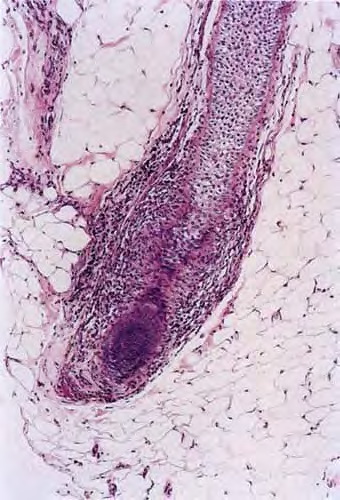

As telogen follicles reenter anagen, they again come under attack from pathogenic lymphocytes, which precipitate premature conversion to catagen once again, so that anagen duration becomes shorter and shorter and the follicles begin to miniaturize . As the follicles decrease in size they become situated more superficially, although often deeper than normal vellus hairs, with their bulbs situated in the mid to lower dermis . With disease chronicity, most of the hairs become miniaturized. Miniaturization and conversion to catagen and telogen leave many collapsed fibrous root sheaths in the subcutis.